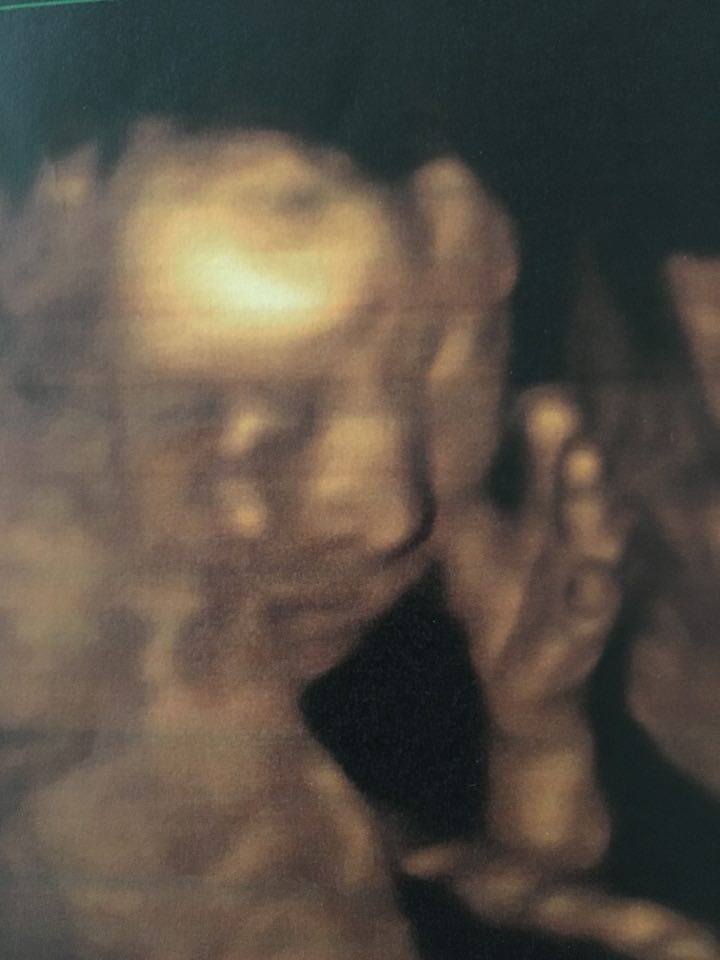

Dziękuję, oby było wszystko ok . Stresuje sie strasznie, jak nigdy... wizyte mam o 11 , wiec juz niedlugo , po dam znac :-)Lookata

Dziekuje bardzo :-)Dzisiaj trzymamy mocno kciuki za Lookate i Zuzanne. Dziewczyny powodzenia! Odezwijcie się po wizytach.